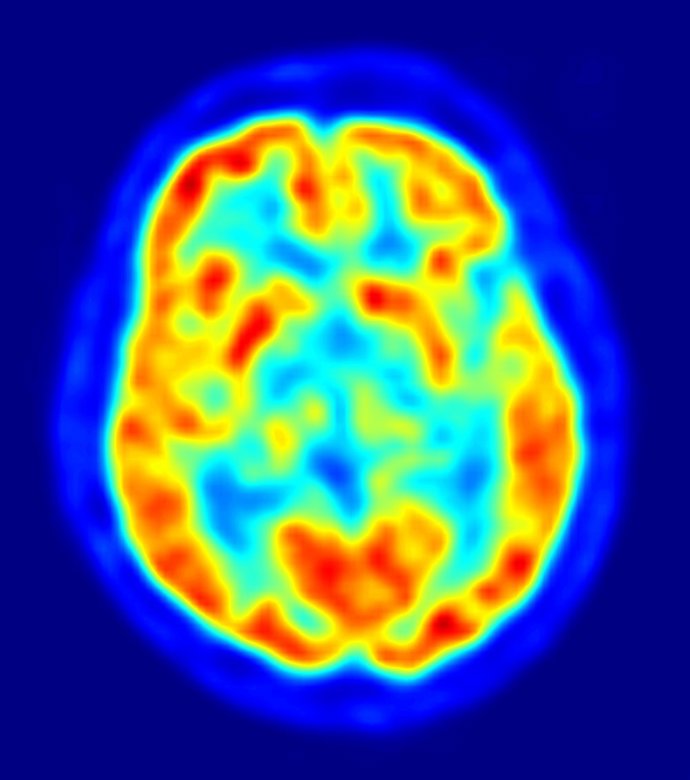

Las diferencias en el comportamiento altruista están relacionadas con la variación en el tamaño y la actividad de una región del cerebro involucrada en la empatía, según un estudio publicado en la revista 'Neuron'. Los resultados también proporcionan una explicación sobre por qué las tendencias altruistas se mantienen estables en el tiempo.

Las personas con facilidad para comprender a los demás son más altruistas; esta capacidad para comprender las perspectivas de otros ha sido previamente asociada con la actividad en una región del cerebro, conocida como unión temporoparietal (TPJ, por sus siglas en inglés). Basándose en estos hallazgos anteriores, Fehr y su equipo se dispusieron a analizar la relación entre el tamaño y la activación de TPJ, y las diferencias individuales en el altruismo.

En el nuevo estudio, los investigadores sometieron a los sujetos a un escáner de imagen cerebral, y les plantearon un juego en el que tenían que decidir cómo repartir dinero, entre ellos mismos y socios anónimos. Los sujetos que tomaron las decisiones más generosas mostraban un TPJ más grande, en el hemisferio derecho del cerebro, en comparación con los sujetos que tomaban las decisiones más egoístas.